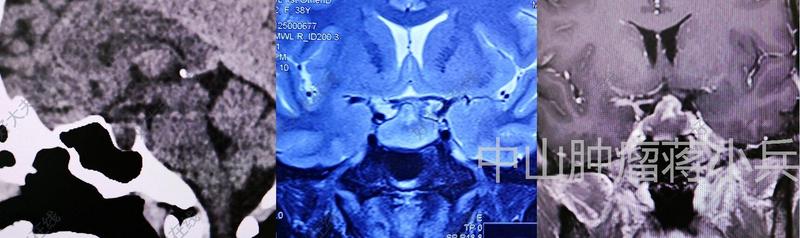

?患者女性,40歲。頭痛反復發(fā)作8年,檢查發(fā)現(xiàn)鞍區(qū)鞍上占位入院。????術前一般情況可,視力視野檢查正常。術前MR提示:鞍區(qū)鞍上第三腦室內(nèi)外囊實性占位。腫瘤已完全占據(jù)第三腦室前部,上方達兩側(cè)室間孔。側(cè)方擠壓腦室壁,和下丘腦區(qū)域關系密切,后方擠壓中腦。考慮顱咽管瘤。CT提示腫瘤部分鈣化。????采取內(nèi)鏡經(jīng)鼻入路顱咽管瘤切除術。術中見腫瘤起源于垂體柄近端、下丘腦區(qū)域。術前影像所見的鈣化部分,大大提升了手術難度,好在沒有重要血管及穿支在鈣化灶內(nèi)穿行,仍能全切腫瘤。????術后患者恢復良好,術后3天復查核磁提示腫瘤全切。術后病理:成釉質(zhì)細胞型顱咽管瘤。(江蘇省人民醫(yī)院神經(jīng)外科陶超)